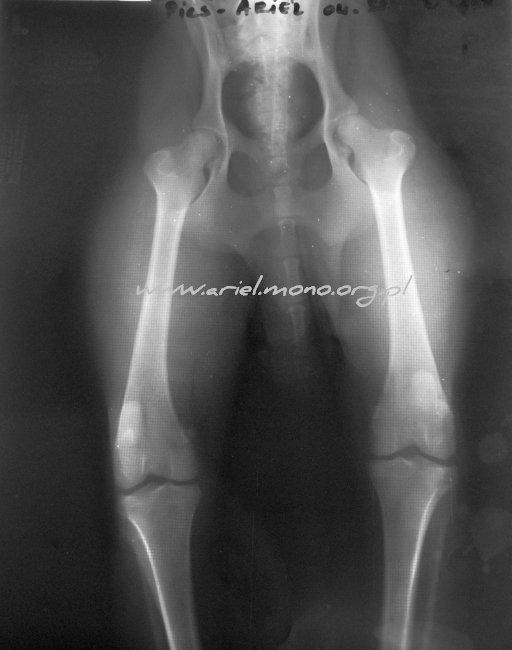

RTG HD/ED

(RTG - FAUNA Łódź, opinia: dr Jan Siembieda)

| Biodra: HD - A |

Łokcie: ED 0 - 0 |

Karta badania

06.05.2011 (FAUNA - Łódź)

Biodra: HD - A

Dodatkowe badanie kontrolne, po tym, jak rozpoznano dysplazję u rodzenstwa.

Zdjęcie RTG